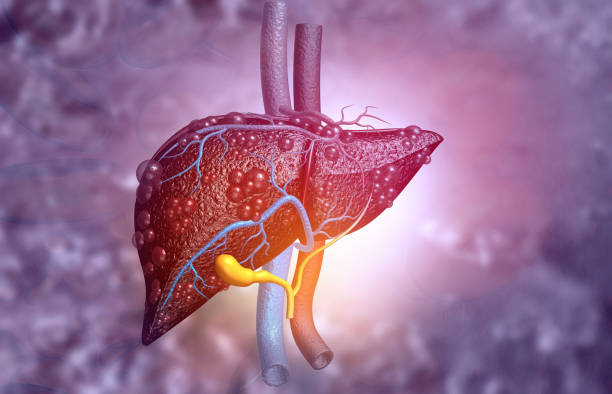

기력 저하와 피로는 간암 초기증상 중 가장 흔한 증상 중 하나입니다. 간은 우리 몸의 대사 기능을 담당하는 중요한 장기 중 하나이며, 간암이 발생하면 간의 기능이 저하될 수 있습니다. 이로 인해 에너지 수요를 충족시키지 못하고 피로감이나 기력 저하가 나타날 수 있습니다.

피부가 창백하고 황색 조절인 경우, 황달이 발생할 수 있습니다. 황달은 간세포의 손상으로 인해 생긴 독소가 적혈구를 파괴하면서 발생하는 증상으로, 피부와 눈꺼풀 등이 노란색으로 변색됩니다.

간암이 발생하면 간 내부의 담관이 막힐 수 있으며, 이로 인해 간세포가 분해되고 혈액 속에 노폐물이 축적됩니다. 이렇게 축적된 노폐물은 체내에서 제거되지 못하고 피부와 눈의 색깔을 노랗게 만드는 황달을 유발할 수 있습니다. 간암에서 황달은 일반적으로 다른 증상과 함께 나타납니다.